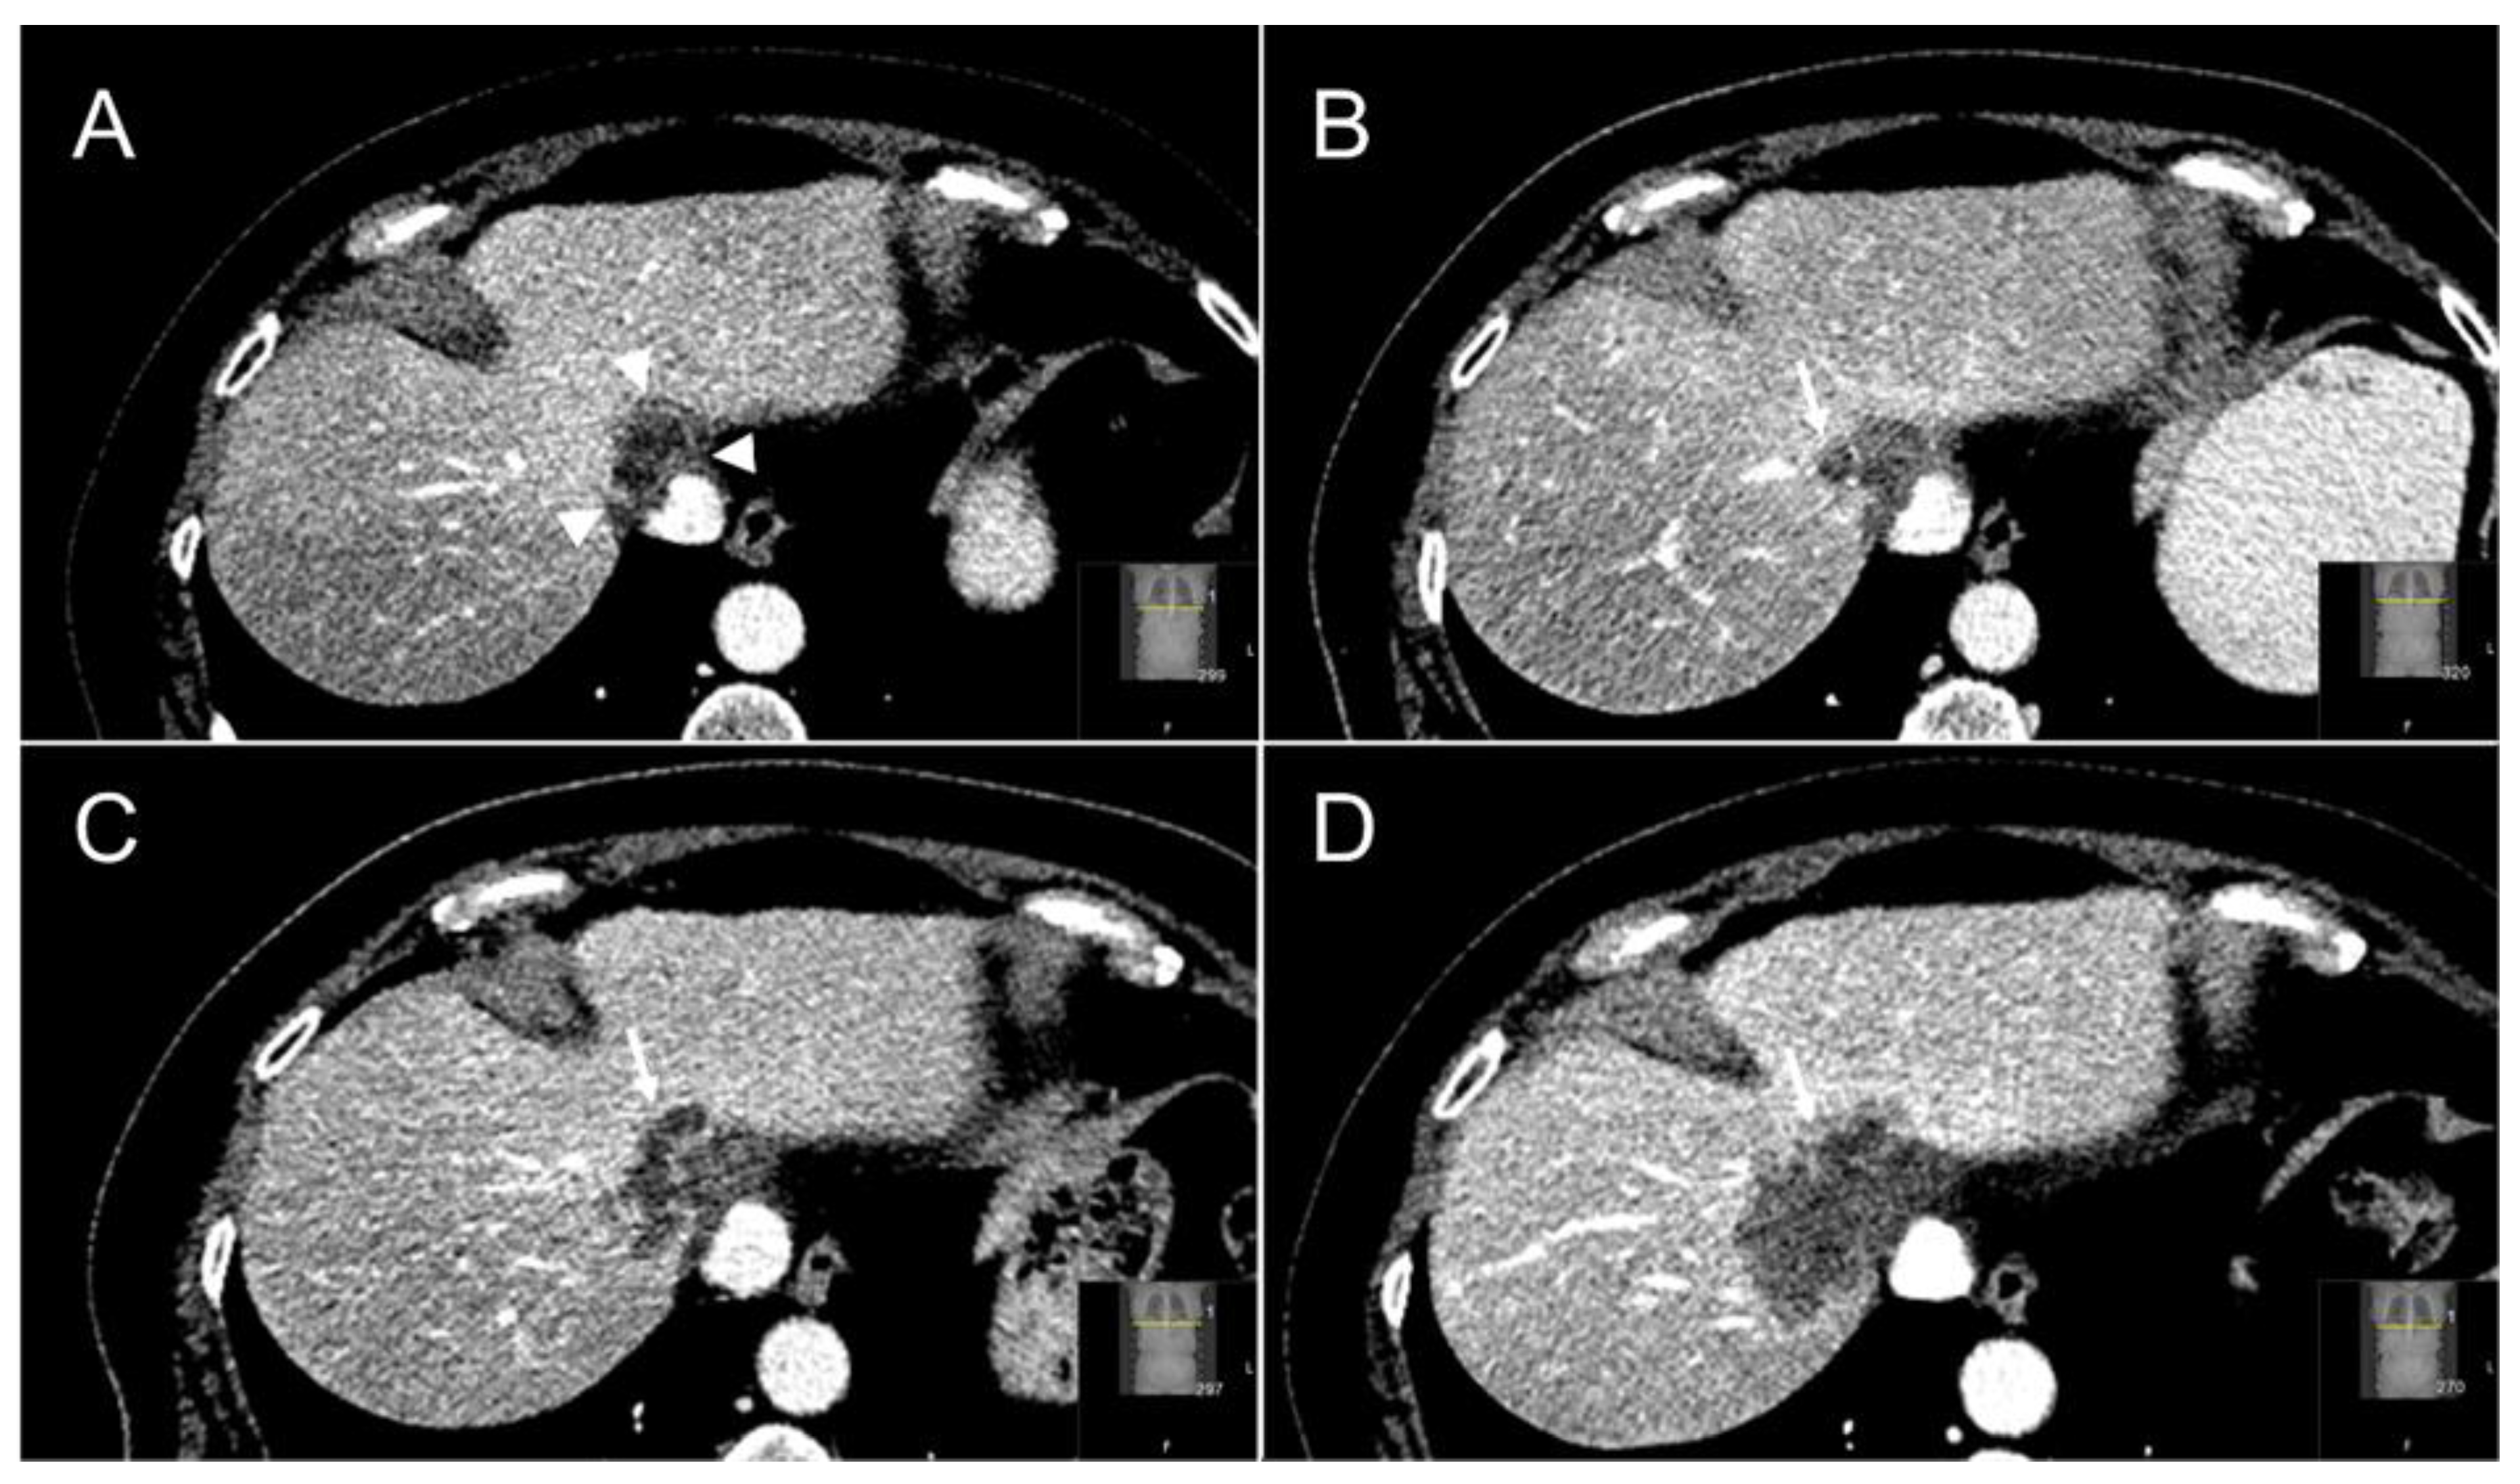

Figure 5.

Follow-up cross-sectional ceCT images of a segment IVa-VIII CRLM treated with SABR. At three months ceCT showed a typical halo sign of hypoattenuation directly surrounding the irradiated, largely necrotic tumor (white arrowheads) and characteristic hyperattenuation of the perilesional liver parenchyma, which correlates with radiation induced hepatic fibrosis (A). At six months a solid ring-enhancing nodular lesion (white arrow) can be appreciated at the right-lateral margin of the irradiated tumor (B). This appearance is highly specific for the presence of local tumor progression post-SABR. Follow-up ceCT at six and 12 months (C,D) further confirmed the local tumor progression.